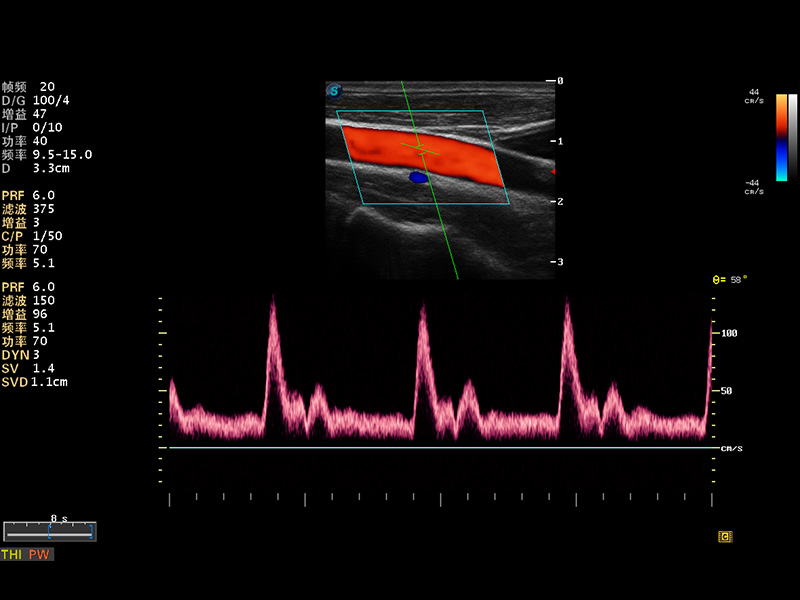

S8 EXP便携式彩色多普勒超声诊断仪是九州酷游研发的高端全身应用型便携彩超。高通道的VIS平台融合可视化(Visual)、智能化(Intelligent)和人性化(Smart)的特点,配以九州酷游自主研发生产的探头大家族,使您能够快速、准确的获得病人信息,提高工作效率的同时减轻疲劳。

成像技术

多波束形成器

μ-Scan微米成像

谐波成像

实时宽景成像

空间复合成像

3D/4D成像